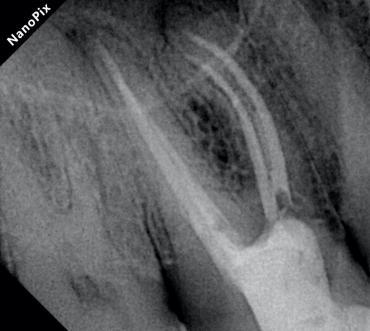

Verifying the precise tug-back fit of the gutta-percha cones.

Radiograph of mesio buccal root canals during obturation

Confirming the dense, 3D fill of the entire root canal system.

Displaying the excellent final result, particularly highlighting the beautiful flow in the mesiobuccal root canals